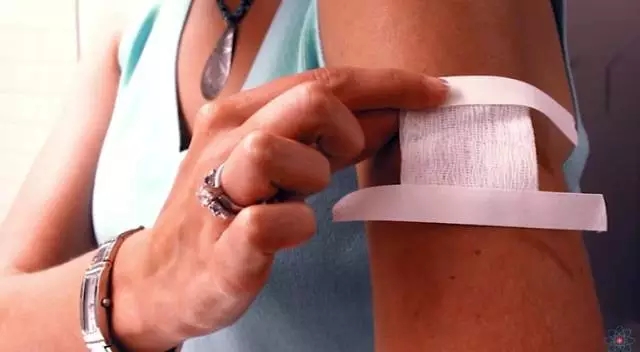

最近他们又研发出了一种高科技的医疗纱布——

电子纱布

不用多想,小编介绍的一定不是一块简单的纱布

它厉害的当然不仅是包扎伤口,

而是可以加速伤口的愈合!

经实验证明,

微量的电流有助于伤口组织的愈合。

因此,“心机”NASA在纱布中加入了一种新型聚合材料

——聚偏氟乙烯(PVDF)

PVDF是一种电活性材料,

它在和人体皮肤接触时会产生轻微的电流。

更神奇的是,

你只要让它升温,或者对它施加压力,

甚至只是吹一口气,

它都会产生电压!

这时伤口周围的细胞,

就会利用纤维整齐的排列结构作为支架,

对伤口四周细胞起到支撑,

再透过极微小电流刺激伤口细胞,

来促进伤口快速愈合。

有了这款纱布就再也不愁了,

未来它也将应用于军事、医疗手术或日常生活中。